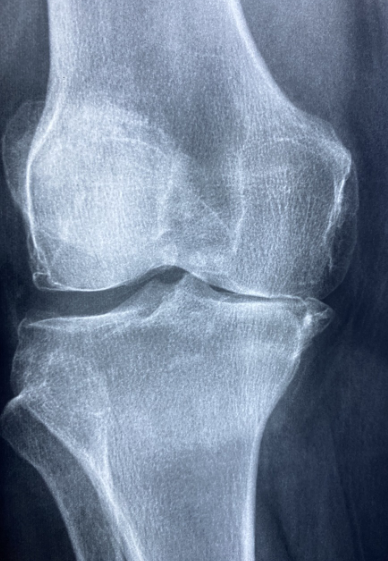

관절건강은 우리 삶의 질과 움직임에 중요한 역할을 합니다. 관절 문제는 일상생활을 어렵게 만들 수 있으며, 통증과 불편함을 초래할 수 있습니다. 이 블로그에서는 관절 건강을 개선하고 연골을 보호하기 위한 식이요법에 대해 알아보겠습니다. 올바른 식단을 통해 관절 건강을 책임지는 방법을 알아보십시오.